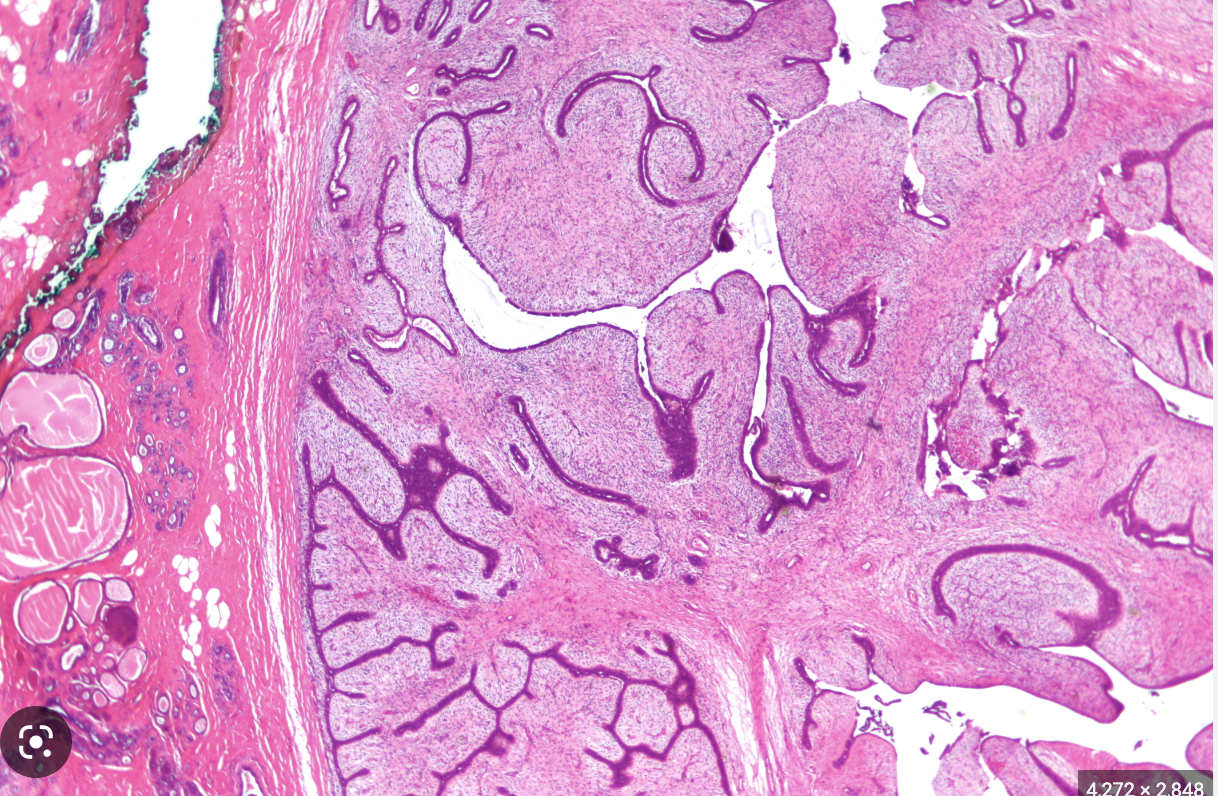

What is a phylloids tumor?

How does it present and how should it generally be managed?

A

Arise from interlobular stroma (like fibroadenomas – can arise within existing

fibroadenomas) with increased cellularity and mitoses

• Present >50yrs as palpable mass

• Low grade or high grade lesions. Mostly relatively benign, but can be locally aggressive therefore –>

excised with wide local excision/mastectomy to limit local recurrence.

• Histology: “branching”/”leaf-like fronds”/”artichoke appearance”